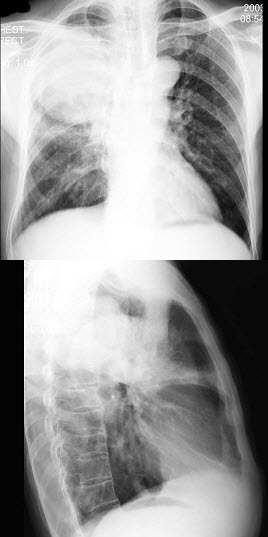

25、单项选择题

男,62岁,咳嗽发热2天,痰中带血,胸片检查如图,最可能的诊断是()

A.左下肺炎症

B.左肺癌伴阻塞性肺炎

C.左肺结核

D.左侧胸膜炎

E.左侧错构瘤